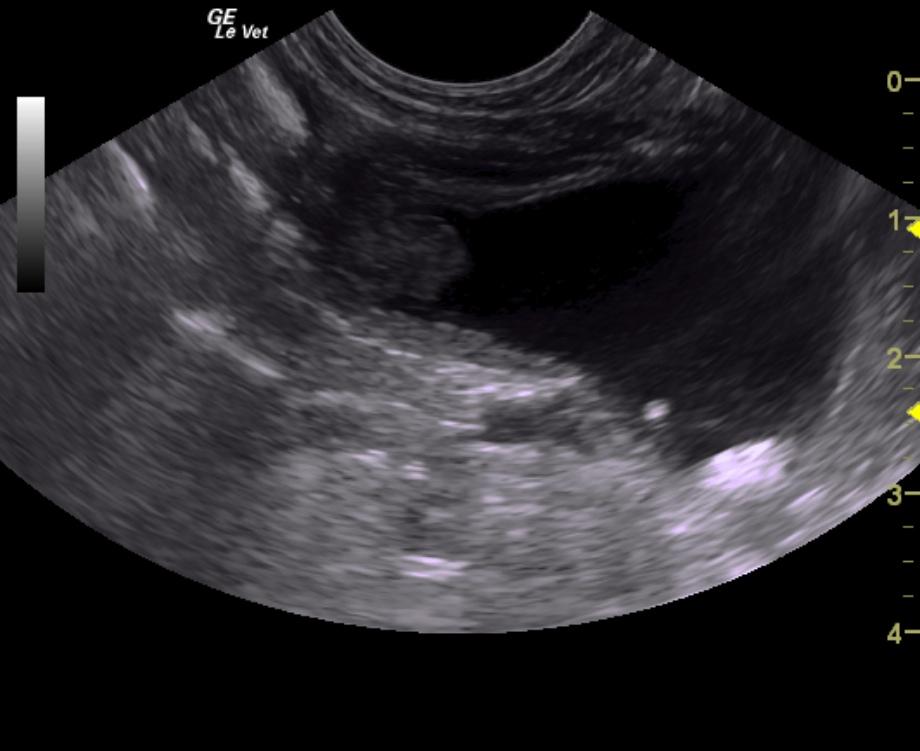

A 14-year-old neutered male Poodle dog was presented for evaluation of chronic hematuria with a history of calcium oxalate calculi and evidence of urinary tract infection.